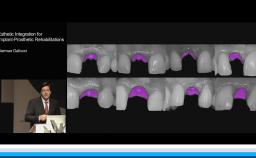

Dr. Gallucci is the Chair of the Department of Restorative and Biomaterial Siences at Harvard School of Dental Medicine. ITI Fellow since 2004, Chair of the ITI Scholarship Center at Harvard.

ITI Study Club UIC Chicago - Lecture with Dr. German Gallucci - “Implant-Prosthodontic Integration in the Esthetic Area”